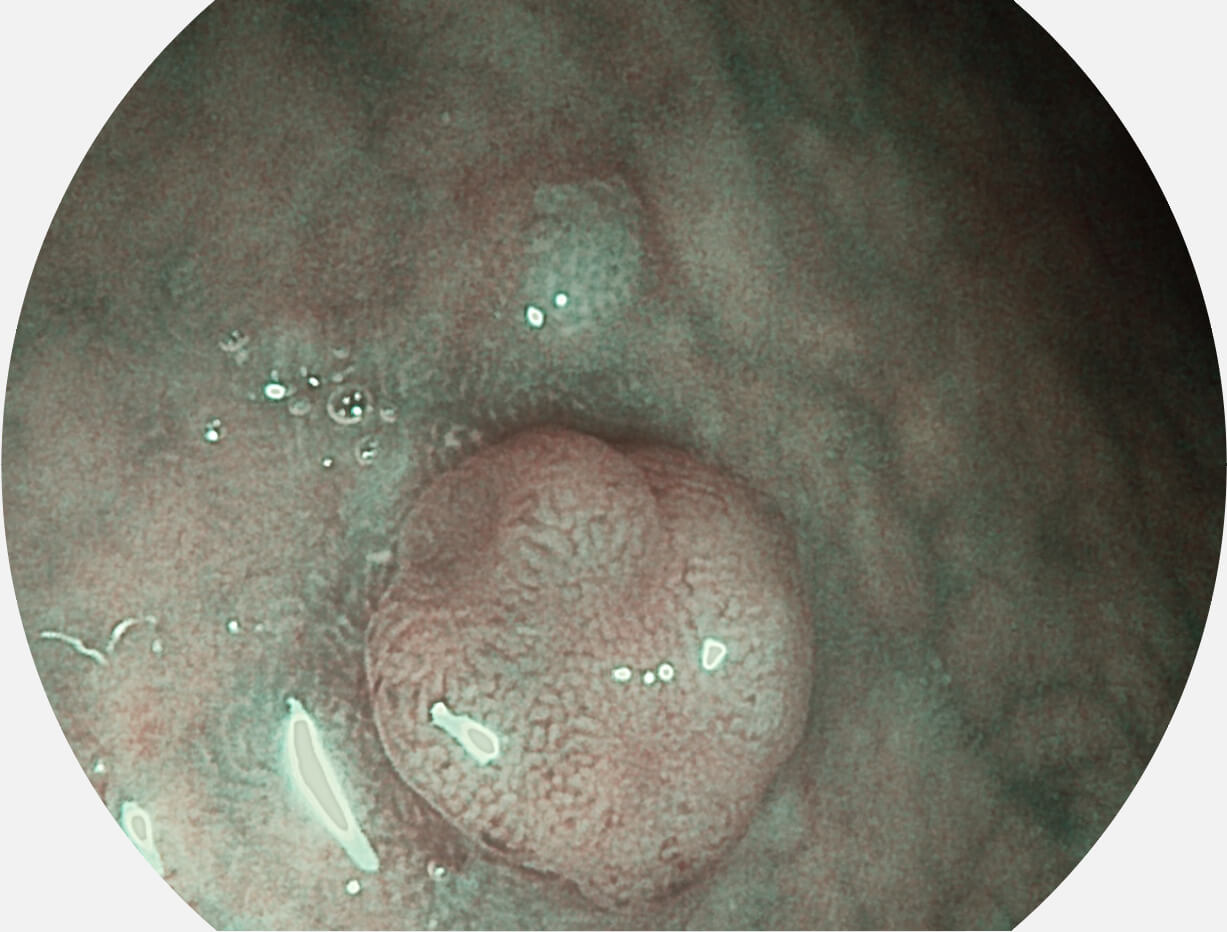

白光图像

VIST图像

强调浅层黏膜结构的同时,保证照明亮度和提升浅层微血管与中层血管颜色对比度,病变边界更清晰。